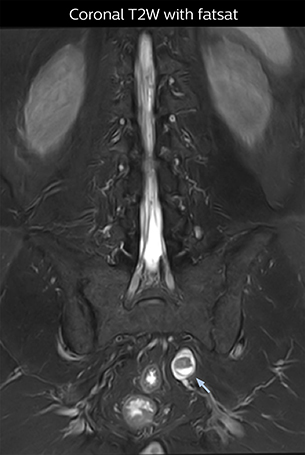

“Although symptoms of typical disc herniation and atypical hernia are very similar, the actual site of herniation is different. It is therefore important to characterize the nerve’s condition both inside and outside of the intervertebral foramina. “Conversely, if we see no abnormality in NerveVIEW, we can assume at least that there is no severe condition that requires surgery. Like this, it can help us avoid unnecessary surgery. NerveVIEW can have a tremendous impact in this way.”

“NerveVIEW is really useful for those cases where a nerve disorder is strongly suspected based on the clinical examination but our regular MRI images do not show any findings. These atypical herniations and spinal canal stenosis, occurring in 5% to 15% of the total lumbar herniation/stenosis cases are our main target when using NerveVIEW,” says Dr. Yabuki.

“The intra-luminal signal of veins, especially around the intervertebral space, can be suppressed well with NerveVIEW. As a result, we can easily observe the detailed nerve structure around the posterior ganglion,” he says. “This is why we use 3D NerveVIEW for intraforaminal stenosis and extraforaminal stenosis/herniation (lateral disc herniation). On the other hand, if herniation is suspected to exist inside the dorsal root ganglion (DRG), balanced TFE or ProSet-FFE is applied. NerveVIEW is not suitable for evaluating the median type of herniation.” The SE-EPI DWI-based method for MR neurography works well for large FOV exams like whole-body MRI, but focal examination of nerves is often limited by the attainable spatial resolution (both inplane and slice direction) and geometric distortion. “3D NerveVIEW achieves higher in-plane resolution – close to our other routine spine sequences – and the source images can be used instead of adding a fat-suppressed T2-weighted sequence,” Tanji says.